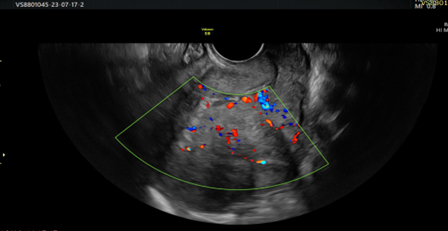

Vascular pattern: single blood vessel with or without laceration, multiple blood vessels of focal origin, multiple blood vessels of multifocal origin, scattered blood vessels(Pictures 1-6).

Picture 4. Doppler view of heterogeneous endometrium with interrupted endometrial myometrial junction and scattered blood vessels.